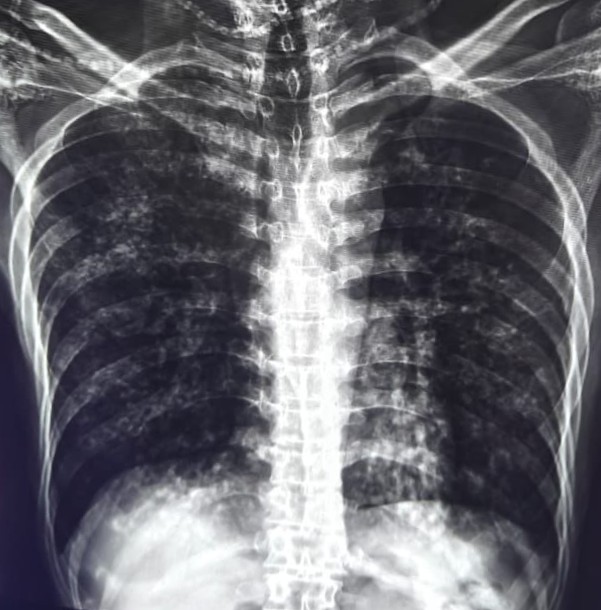

| 219 | IGGMC, Nagpur, Nagpur | P2 | 29-4253 | BACCHO CHAUDHARI | Consent taken on Paper | 47 Yrs. |

Provisional Diag : MILLIARY TB

Final Diag : BILATERAL INFILTRATION WITH MILLIARY SHADOWS |

TB Case (Confirmed) | BILATERAL INFILTRATION WITH MILLIARY SHADOWS | Abnormality visible on x-ray |

View |

|||